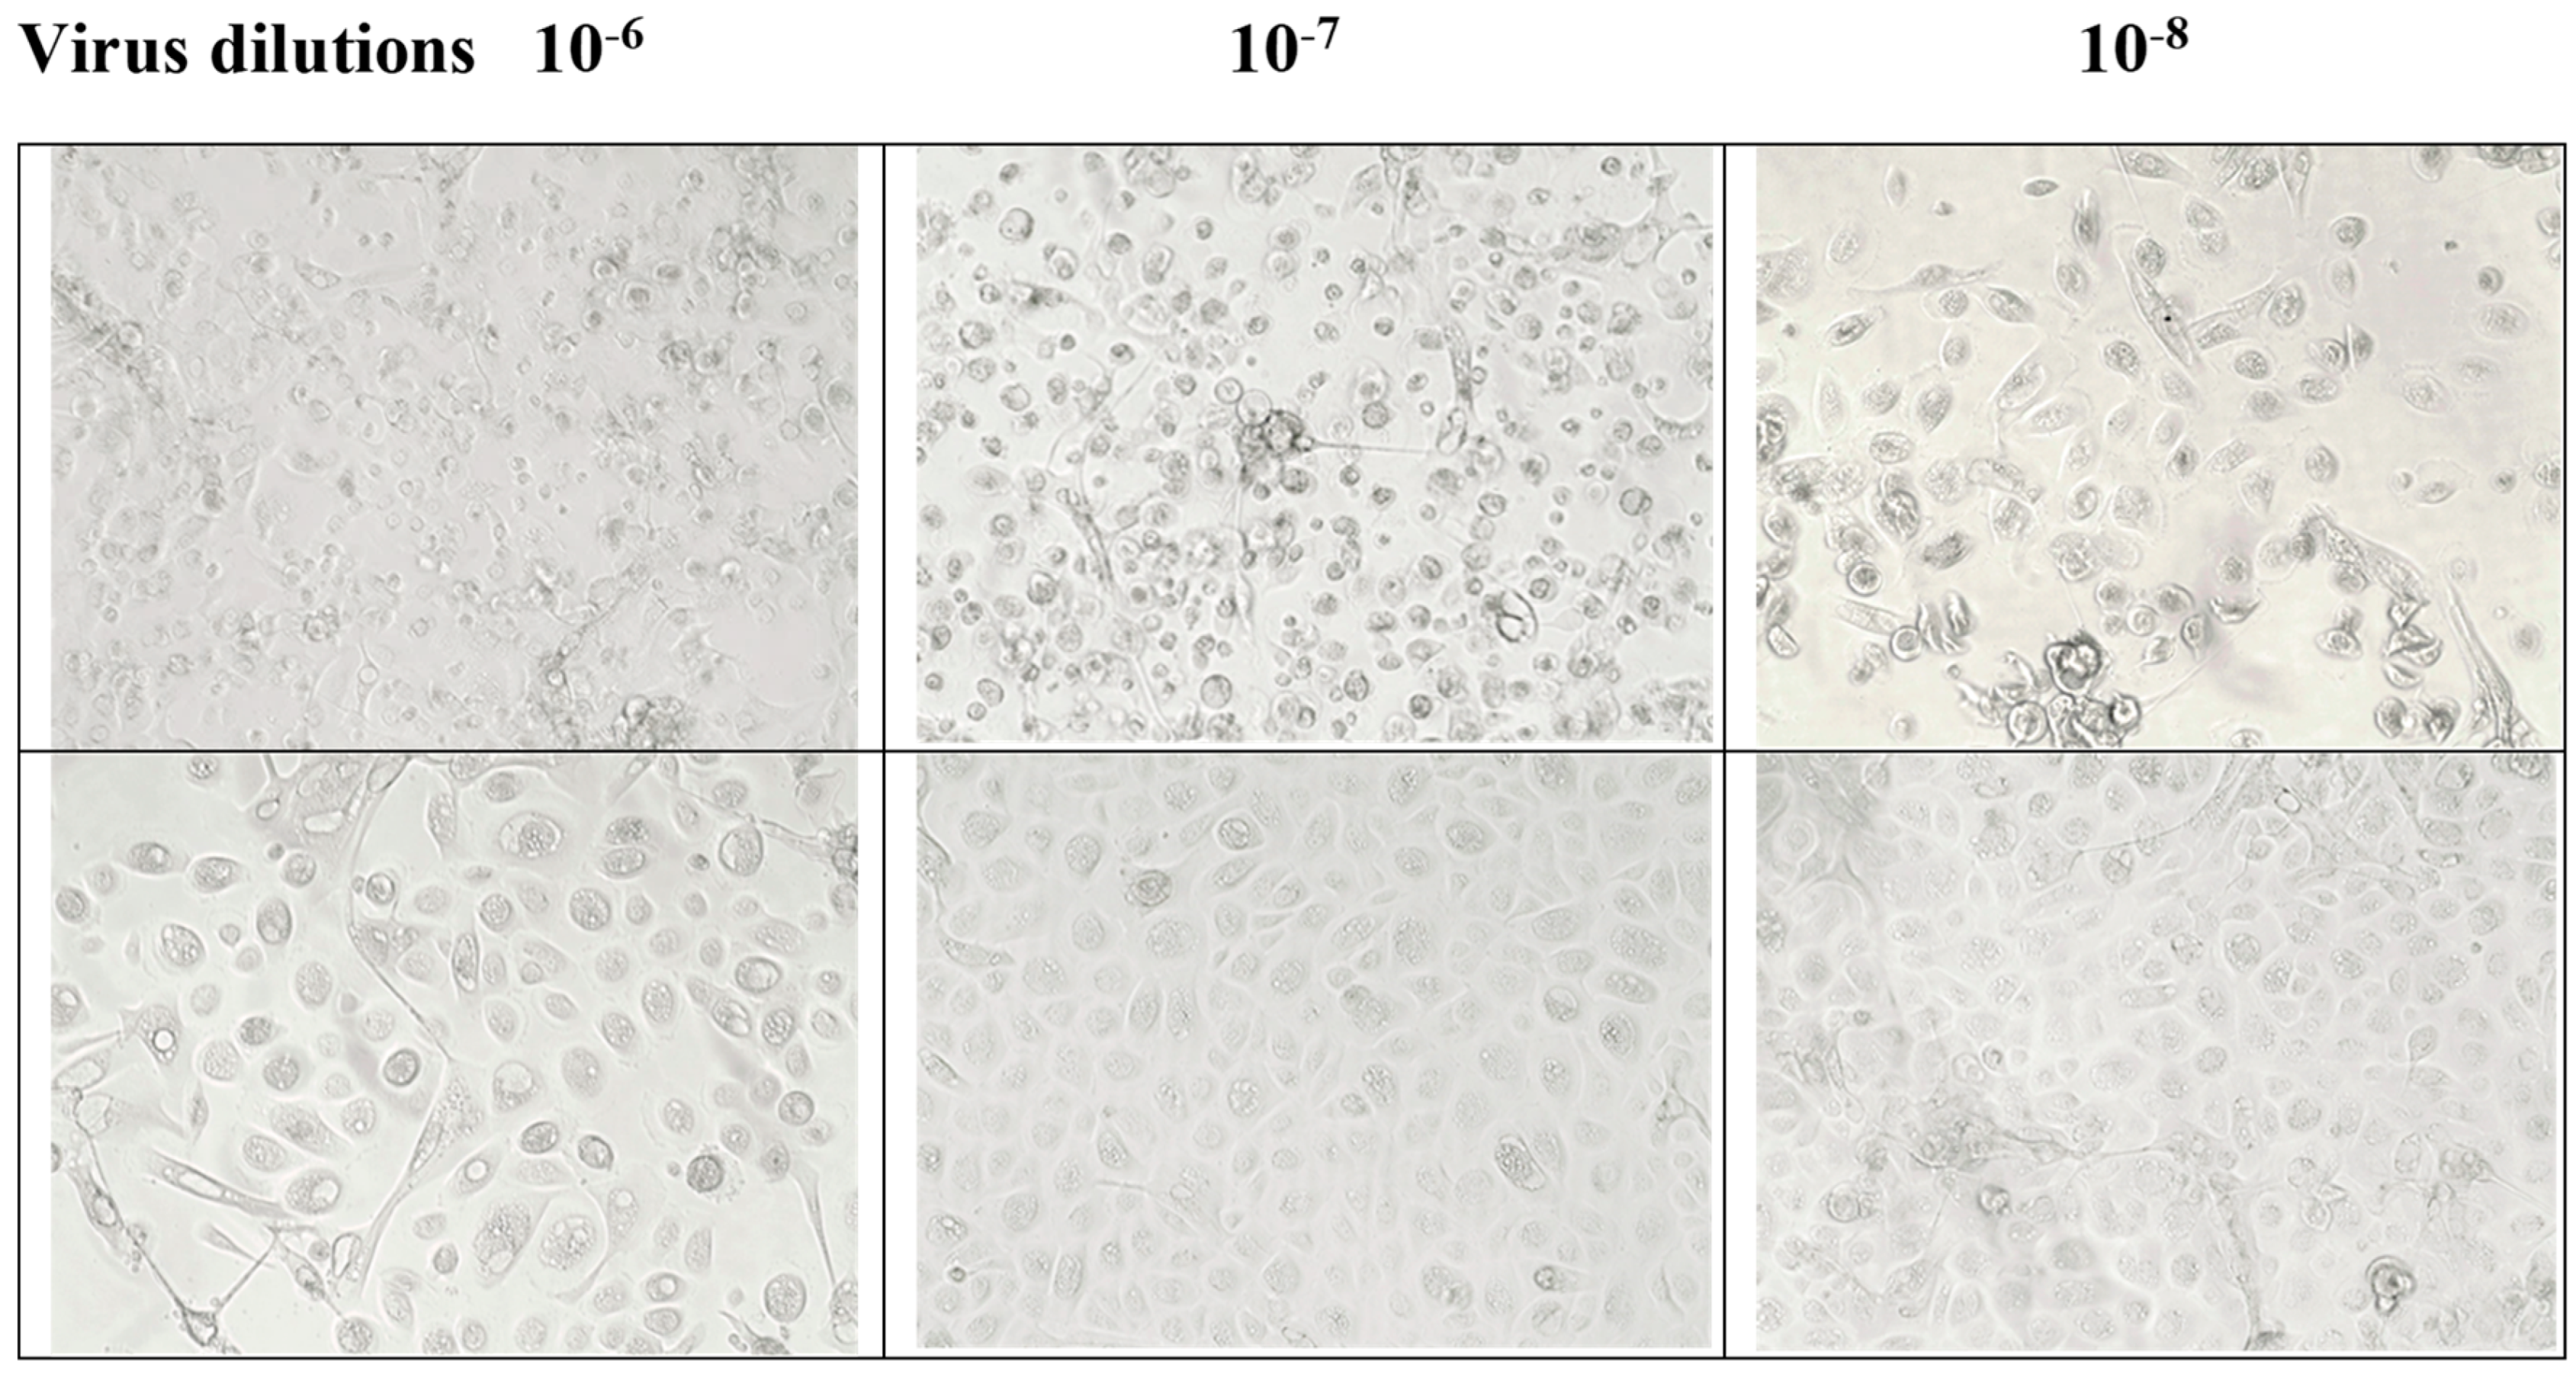

3.2. Contact Inhibition